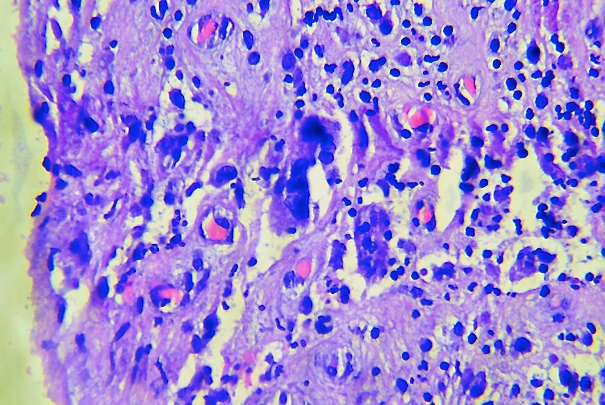

Morawietz et al. (12) propusieron una nueva clasificación para la evaluación y análisis del tejido periprotésico, con el objetivo de obtener criterios para definir los tipos de membranas y facilitar el diagnóstico histopatológico de rutina. Morawietz et al., (12) (13) describieron cuatro tipos de membranas periprotésicas. La membrana tipo I, inducida por partículas de desgaste. Se caracteriza por la presencia de partículas de cuerpo extraño, abundantes macrófagos y células gigantes multinucleadas en al menos 20% del tejido. Se pueden identificar partículas de metil metacrilato, dióxido de zirconio o sulfato de bario (Figura 1). La tipo II o infecciosa que se observa la presencia de tejido de granulación con abundantes leucocitos neutrófilos y células plasmáticas, sin partículas de cuerpo extraño (Figura 1). La membrana tipo III o combinada pues Contempla aspectos del tipo I y II en forma simultánea (Figura 1) y la tipo IV o indeterminada ya que muestra parámetros morfológicos diferentes a la tipo I y la tipo II, con mayor presencia de abundantes fibras de colágena, fibrina, fibroblastos y macrófagos (Figura 1). El objetivo de este estudio está encaminado a caracterizar las membranas periprotésicas de cadera en base a la clasificación de Morawietz, mediante análisis histopatológico y bacteriológico.

A) Preparación histológica de membrana periprotésica de cadera tipo I, con macrófagos y células gigantes multinucleadas de tipo cuerpo extraño, partículas de material protésico

B) membrana periprotésica de cadera Tipo II, con tejido de granulación, fibroblastos, proliferación de vasos, edema, infiltrado inflamatorio de predominio neutrófilos.

C) membrana periprotésica de cadera Tipo III, con reacción a partículas de material protésico y reacción inflamatoria con neutrófilos.

D) membrana periprotésica de cadera Tipo IV con tejido conectivo poco celular rico en colágena, fibrina en la superficie, macrófagos y fibroblastos y sscasos neutrófilos (tinción hematoxilina-eosina, x10)